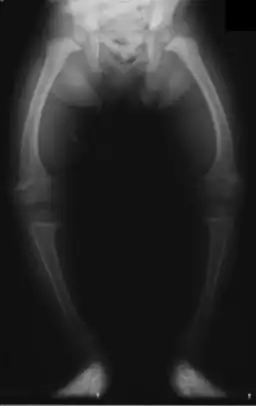

| Radiografia de criança de dois anos com raquitismo, com fémures arqueados e diminuição da densidade óssea | |

Raquitismo é uma doença metabólica caracterizada por deformações dos ossos em crianças.[4][1] Os sintomas mais comuns são pernas arqueadas, atraso no crescimento, dor nos ossos, deformações cranianas e dificuldade em dormir.[1][2] Entre as possíveis complicações estão fraturas ósseas, espasmos musculares, escoliose ou deficiência intelectual.[1][2]

A causa mais comum de raquitismo é a deficiência de vitamina D.[1] Esta deficiência pode ser o resultado de uma dieta com uma quantidade insuficiente de vitamina D, pele de tom escuro, pouca exposição solar, falta de suplementação com vitamina D nos casos em que o bebé é amamentado em exclusivo, doença celíaca e algumas doenças genéticas.[1][2] Entre outros fatores estão a deficiência de cálcio ou de fósforo.[3][5] O mecanismo subjacente envolve a insuficiente calcificação da placa epifisária.[6] O diagnóstico baseia-se geralmente em radiografias e análises ao sangue para detectar a presença de baixos níveis de cálcio, baixos níveis de fósforo e elevada fosfatase alcalina.[1]